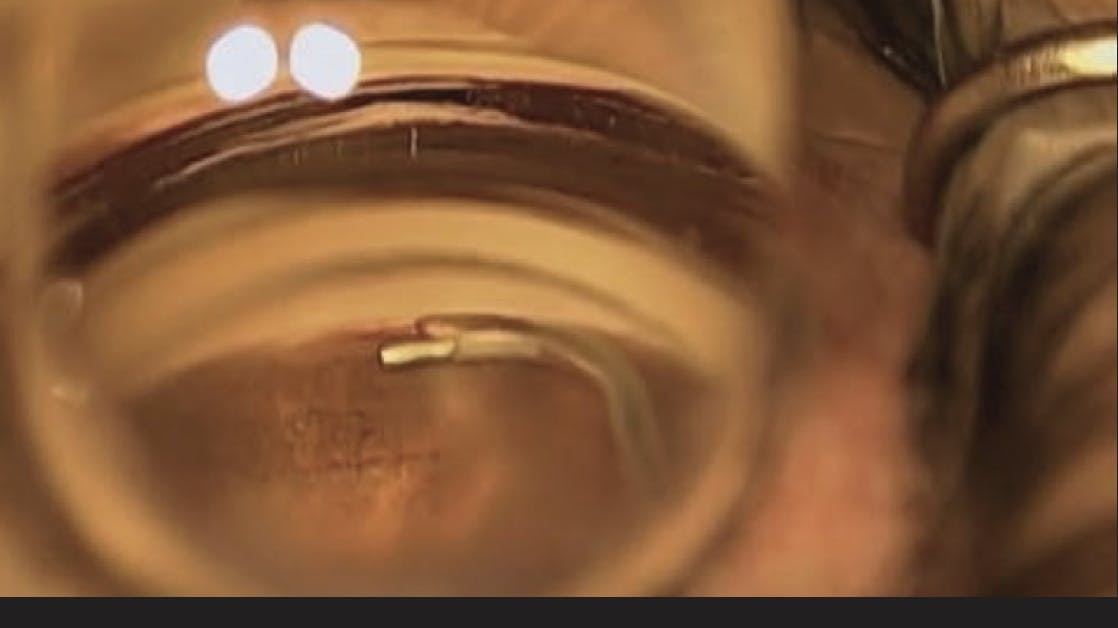

Hydrus Microstent Placement Tips

Dave Woods, MD